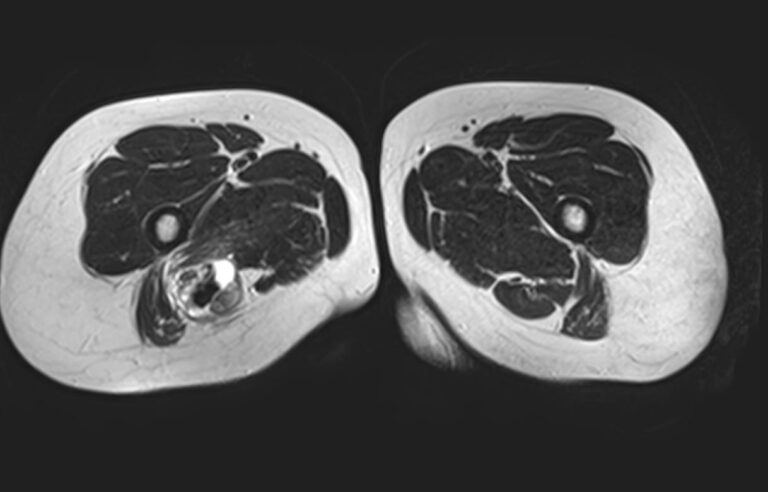

Магнитно-резонансная томография применяется для обследования мягких тканей верхних и нижних конечностей, включая кожу, подкожно-жировую клетчатку, мышцы, фасции, межфасциальные пространства, сухожилия, связки, сосудистую систему, лимфоузлы и лимфатические протоки, нервные волокна, надкостницу и костный мозг.

Кроме того, имеет значение показатель индукции магнитного поля томографа. Наша клиника оснащена современным высокопольным томографом последнего поколения TOSHIBA VANTAGE TITAN 1,5 Тесла. Высокая индукция магнитного поля обеспечивает повышенную четкость изображений при обследовании мягких тканей конечностей. За счет послойного сканирования в различных плоскостях с шагом от 1 мм и последующего преобразования данных в объемные изображения томограф обеспечивает выявление мельчайших изменений в тканях. Это позволяет проводить диагностику различных заболеваний на самых ранних стадиях.